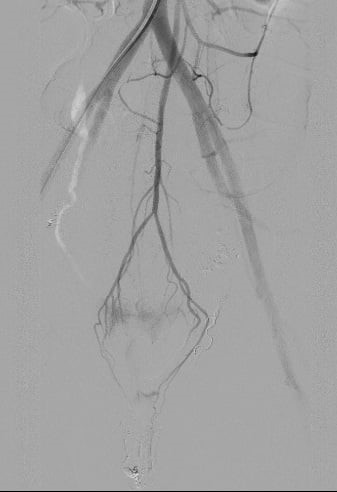

Sau nút mạch động mạch mạc treo tràng dưới

Sau 90 phút cân não, bằng tất cả trí lực và hệ thống trang thiết bị hiện đại, kíp bác sĩ Trung tâm Điện quang đã làm nên kỳ tích trong lịch sử điện quang can thiệp Việt Nam. Nhớ lại khoảnh khắc “đấu trí” với tử thần đó, BSCKII. Phan Hoàng Giang, người trực tiếp thực hiện ca can thiệp cho biết: “Đây là lần đầu tiên, chúng tôi gặp trường hợp chảy máu sau đẻ mà nguồn gốc lại từ động mạch mạc treo tràng dưới. Ca lâm sàng này rất hiếm gặp trên thế giới. Ca được báo cáo lần đầu tiên là vào năm 2015. Và trong một nghiên cứu lên đến 783 bệnh nhân thì chỉ có 8 bệnh nhân mắc (chiếm 1% các trường hợp chảy máu sau đẻ). Với những bệnh nhân đã cắt tử cung càng khó khăn trong quá trình tìm động mạch tử cung nhằm cầm máu và gây tắc. Ca sản phụ này khá phức tạp và mất nhiều thời gian hơn so với ca chảy máu sau đẻ thông thường. Bình thường, chúng tôi chỉ gây tắc nhánh mạch tổn thương và cầm máu tạm thời động mạch chậu trong hai bên. Tuy nhiên với bệnh nhân này, chúng tôi cần tìm thêm các nhánh chảy máu quanh trực tràng, gồm 6 nhánh mạch 2 bên: động mạch trực tràng trên, động mạch trực tràng giữa và động mạch trực tràng dưới. Sau khi xác định được nhánh chảy máu, chúng tôi phải lựa chọn vật liệu gây tắc mạch cũng như vị trí can thiệp để không bị hoại tử trực tràng”. Sau 36 tiếng theo dõi an toàn, sản phụ đã được xuất viện, trở về nhà cùng chồng và 3 con thơ.